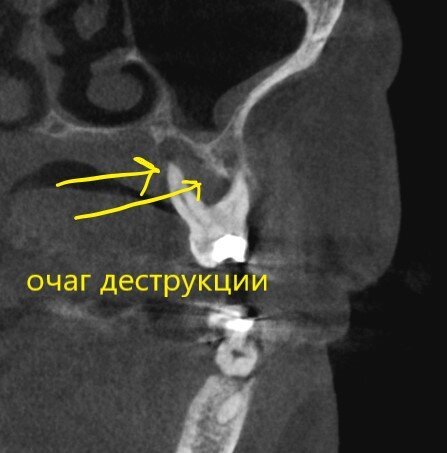

Пародонтит + периодонтит.

Хуже пародонтита может быть только присоединившийся к нему периодонтит (воспалительный процесс на верхушке корня/корней, в народе "киста") - вот уж где разрушение кости глобальным образом проявляется.

Периодонтит.

Кортикальные пластики утеряны, жаль.